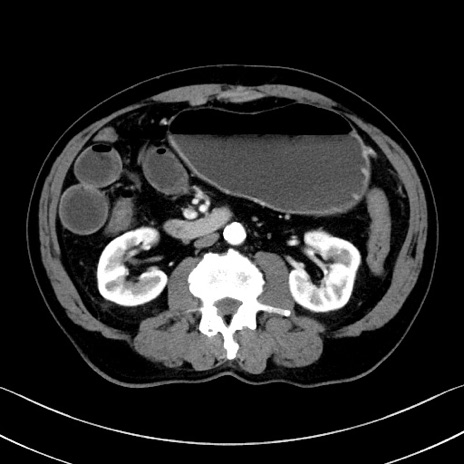

症例35(横断像)

【症例】70歳代 男性

【主訴】腹部膨満、嘔吐

【現病歴】昨日より腹部膨満感出現。本日増悪し、仙痛出現。嘔吐あり、受診。

【既往歴】糖尿病、胆摘後

【身体所見】BP 149/80mmHg、HR 74/min、BT 35.9℃、腹部:膨満、軟、圧痛なし。腸雑音減弱あり。上腹部正中切開瘢痕あり。

【データ】WBC 13500、CRP 1.72